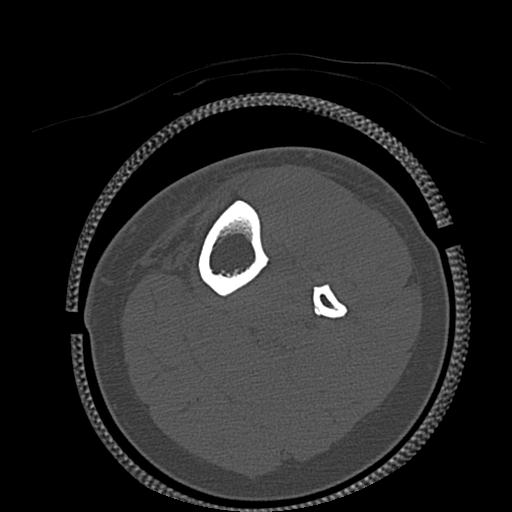

110286 2/17 股関節 2R 74歳女性 右人工骨頭

82084 1/14 1/20 股関節 2R 78歳男性 右人工骨頭

102811 1/13 股関節 2R 1/19 2R 80歳女性 右DHS